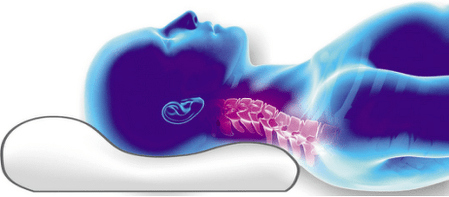

- Використання неправильних подушок під час сну.

Ортопедична подушка при шийному остеохондрозі - річ незамінна, так як вона дозволяє досягти повного розслаблення м'язових волокон і уникнути защемлення судин, що призводить до погіршення кровообігу. Якими повинні бути ортопедичні подушки? Ось його ознаки:

- Шийна подушка дбайливо підтримує голову і створює правильну опору для шийних хребців. Ортопедична подушка має 2 підкладки різної висоти, для

різні положення тіла, придатні для сну як на спині, так і на боці. Група фахівців розробила конструкцію подушки з виїмкою (одною або двома) під плечем для належної підтримки шиї та голови під час сну, особливо на боці. Форма з виїмкою для плеча допомагає знайти зручне положення і тримати хребет рівним.